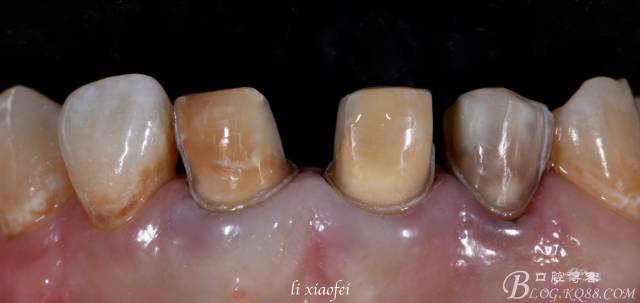

B:牙體預(yù)備

貼面預(yù)備的術(shù)前設(shè)計(jì)也是非常重要的,比如這個(gè)病例#11、#21、#22牙體上都有樹脂,首先應(yīng)該去處原有樹脂然后從新恢復(fù)原牙樹脂形態(tài),因?yàn)闃渲瑫r(shí)間長以后會(huì)引起老化并且可能引起微滲漏,所以我設(shè)計(jì)的是包繞樹脂形態(tài);再有就是貼面要求牙體預(yù)備量為0.3-0.5mm,這種內(nèi)源性染色最好預(yù)備至0.5mm,用牙周探針檢查預(yù)備量或者M(jìn)OCK UP檢查預(yù)備量,唇面按照牙齒固有形態(tài)制備,鄰面“L形”制備。為了不破壞牙齦,可以在徹底牙體預(yù)備完成以后置放排齦線,第一根中空000,完全沒入,第二根選擇實(shí)心排齦線,從唇側(cè)觀能暴露肩臺(tái)即可;排齦線旋轉(zhuǎn)式旋入,盡量不要撕裂上皮組織;暴露肩臺(tái)后可以用釉質(zhì)鑿去處邊緣“菲邊”。